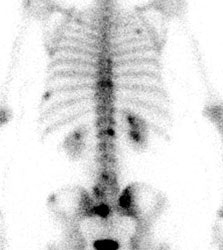

FDG PET exam results in breast cancer patient guide therapy: The patient shown below was a 40 year old female who had undergone lumpectomy and adjuvant chemo/radiation therapy for breast cancer. Ten months later the patient began to experience pain in the right shoulder. A bone scan and CT scan were interpreted as negative. The FDG PET exam revealed numerous foci of tracer accumulation within the right axilla and chest consistent with metastatic disease. As a result of the PET exam findings the patient was treated with another course of chemo/radiation therapy. The exam was performed on a Siemens ECAT EXACT PET scanner; 10 mCi FDG, and 5 bed positions. Case courtesy of Rush-Presbyterian-St. Luke's Medical Center, Chicago, IL and CTI. |